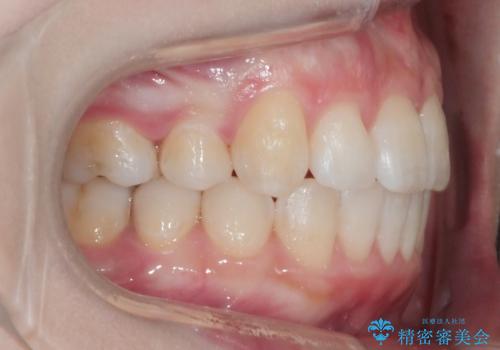

ワイヤー矯正 抜歯本数を最小限にし、八重歯のない歯並びに

- 上顎の八重歯が気になるとのことで来院されました。

左側のかみ合わせは、歯1本分かみ合わせが前にずれていました。上顎左右の奥歯を2本抜歯しています。

八重歯でがたつきは重度でしたが、きれいな歯並びにすることができました。

がたつきだけでなく、奥歯の噛み合わせのずれの調整もしっかり行いました。

奥歯のずれの調整は時間がかかりますが、矯正後の歯並びの安定度が向上します。